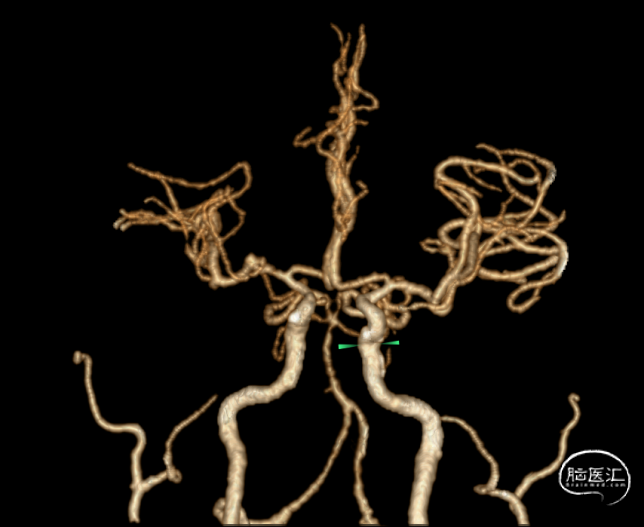

CTA:左侧颈内动脉、左侧大脑中动脉闭塞。

全身麻醉,右侧股动脉入路,应用泥鳅导丝、单弯造影导管辅助下将6F 90cm长鞘置于左侧颈总动脉末端,继续在泥鳅导丝及该长鞘辅助下将6F 125cm 通桥银蛇®颅内支持导管置入右侧颈内动脉C3段、长鞘置于颈内动脉C1段,然后在路图下,0.014" 北斗SS™神经血管导丝引导下将微导管小心通过闭塞段置于右侧大脑中动脉上干M2段,并造影确认真腔。

然后经该微导管置入通桥蛟龙®取栓支架 6.0*30mm,于闭塞段定位并完全释放;造影见血管较前恢复通畅。

至支架与血栓充分嵌合后,支架锚定下将6F 125cm 通桥银蛇®颅内支持导管向前送至大脑中动脉M1段起始部血栓近端,回撤微导管及支架系统,同时中间导管尾端行负压抽吸回撤,取出大量血栓;即刻造影见左侧颈内动脉大脑中动脉系统血流恢复,远端血流mTICI 3级。